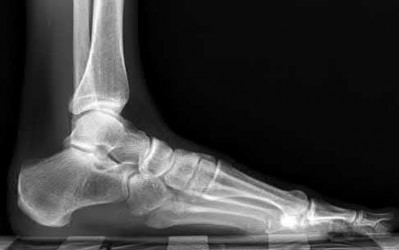

2. # A 35-year-old woman is involved in a head-on collision while driving. Initial radiographs are shown in Figures 8a and 8b. Injury to what vessel increases the risk for osteonecrosis of the injured bone?

5. Artery of the tarsal sinus Corrent answer: 4

The patient has a Hawkins type III talar neck fracture-dislocation with a risk of osteonecrosis ranging from 69% to 100%. Anatomic studies have shown that the artery of the tarsal canal supplies the lateral two thirds of the talar body.

The other vessels listed provide no significant contribution to the talus.